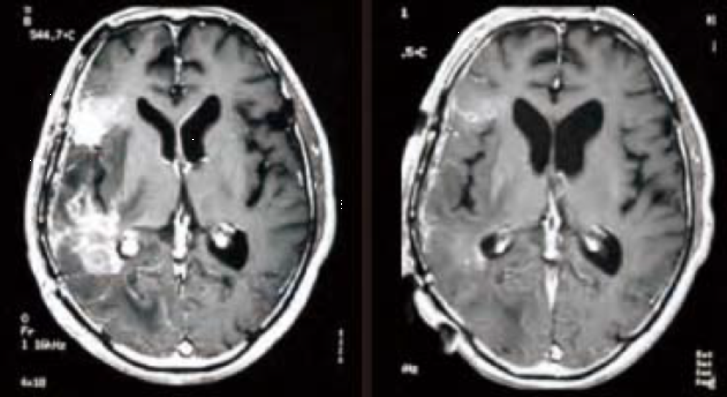

脑肿瘤(代表案例:恶性脑胶质瘤)

恶性脑肿瘤,尤其是恶性脑胶质瘤,是BNCT临床研究中被寄予了很高期望的适应症。由于BNCT可以一次进行大剂量的中子照射,因此在治疗后短期(约治疗2天后)内就能出现剧烈的肿瘤反应(MRI图像中增强病灶缩小或消失)。

图片

BNCT治疗前

BNCT 治疗48小时后

(图像来源 : 关西BNCT共同医疗中心)